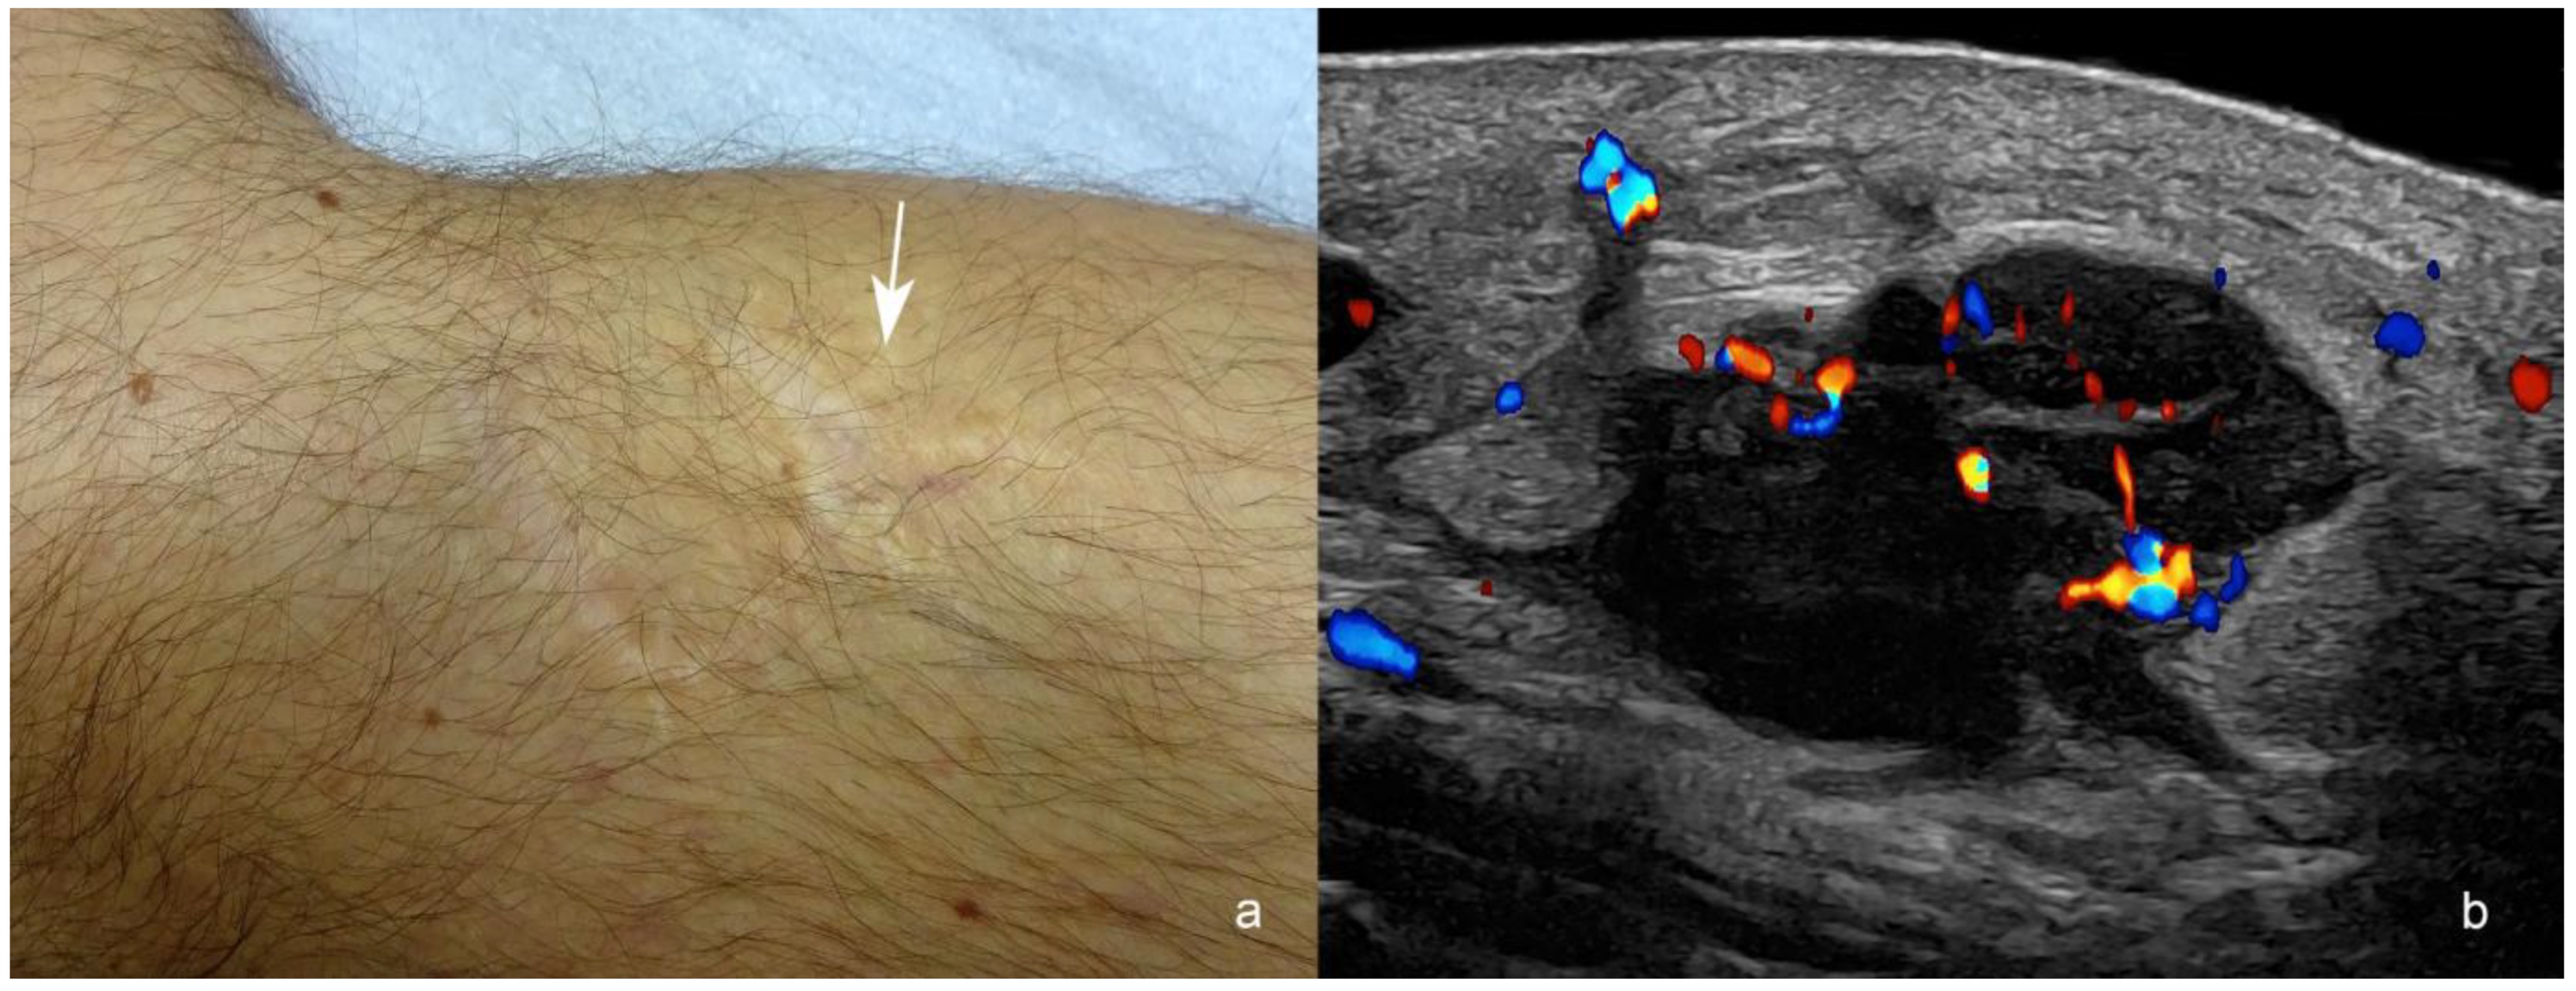

Post Operative Recurrence or Remnant BCC

- Catalano, O.; Crisan, D.; Díaz, C.P.G.; Cavallieri, F.; Varelli, C.; Wortsman, X. Ultrasound Assessment of Skin Tumors Local Recurrence. J. Ultrasound Med. 2023, 42, 2439–2446. [Google Scholar] [CrossRef] [PubMed]